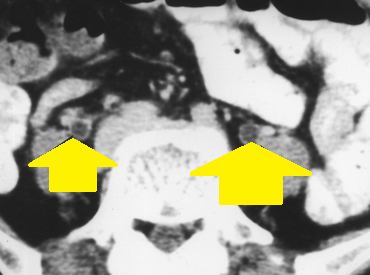

Αξονική τομογραφία οπισθοπεριτοναίου. Κίτρινα βέλη – Αμφοτερόπλευρη διάταση ουρητήρων. Ευγενική παραχώρηση Dr. V. Penopoulos.